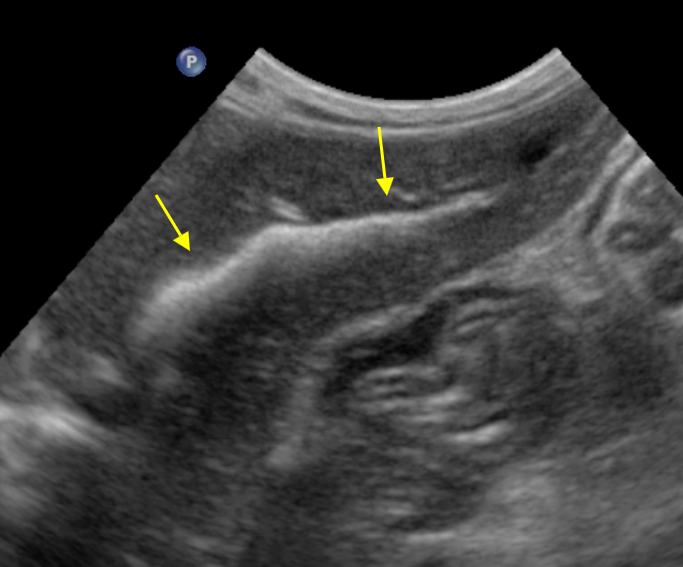

ultrasonography

branched intrahepatic bile duct stone